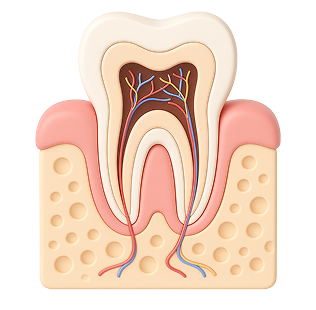

Пульпит – это воспаление пульпы – нервно сосудистого пучка, который находится внутри зуба и питает его.

- Самой распространенной причиной пульпита является невылеченный вовремя кариес. Кариозный процесс усугубляется, кариозная полость углубляется, в конце концов разрушается пульповая камера, в которой заключен «нерв». Бактерии из кариозной полости попадают внутрь и инфицируют пульпу — начинается воспаление.